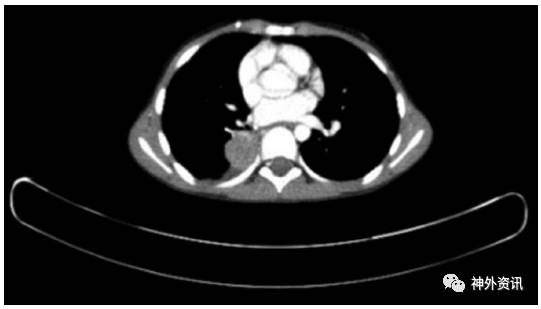

5岁男性患儿,诊断为斜坡脊索瘤(图1)。5年前行经口入路完全切除肿瘤(图2),术后进行质子束放疗。病理学检查报告为典型的脊索瘤,免疫组化提示角蛋白强阳性、上皮膜抗原强阳性、S-100免疫反应阴性和MIB-1标记指数为10%(图3)。术后因脑脊液漏反复出现脑膜炎,给予抗生素治疗后好转。接着继发交通性脑积水,通过脑脊液VP分流术降颅内压。术后5年发现肺部结节(图4),手术活检提示为低分化的脊索瘤,免疫组化结果和原发部位脊索瘤相似,即角蛋白强阳性和上皮膜抗原强阳性(图5),表明斜坡脊索瘤颅外转移。随后相继发生胸壁和颅骨转移。由于大部分脊索瘤mTOR通路激活,所以给患者使用伊马替尼联合雷帕霉素化疗后,肿瘤缩小,疼痛有所减轻。但是,9月后出现额部头皮肿物,并导致附近的VP分流管周围皮肤破溃。遂行头皮肿物切除和皮瓣转移术,以防止分流管暴露。免疫组化提示PD-L1高表达,即行PD-L1单抗治疗,胸痛明显缓解。6月后又出现新发的肺部转移灶,疼痛明显。免疫组化和基因检测为INI-1缺失,应用EZH2进行晚期解救治疗,疗效尚待评价。

图4. 术后4.6年PET-CT结果显示右肺下叶转移瘤。